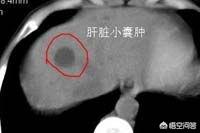

Plus tard, l'échographie a été perfectionnée et sa soi-disant "tumeur du foie" s'est avérée être un kyste du foie. Je lui ai expliqué et il a été soulagé des soucis qui l'avaient perturbé pendant plus de 2 ans. ......

Ce type de kystes hépatiques, qui sont des lésions bénignes, ne présentent généralement pas de symptômes cliniques évidents et ne sont découverts qu'accidentellement lors d'une échographie ou d'un examen par tomodensitométrie, et seuls certains kystes de grande taille, qui provoquent des douleurs abdominales ou une gêne abdominale chez les patients, sont également généralement féminins.

En cas de kystes hépatiques inexpliqués, il est conseillé de se rendre à l'hôpital pour une tomodensitométrie améliorée du foie et de consulter un chirurgien hépatobiliaire pour mieux comprendre la situation. Il ne faut pas être comme le patient que j'ai rencontré dans l'article précédent, qui était déprimé tous les jours jusqu'à ce qu'il connaisse la vérité.

En général, si le kyste est petit et que le patient ne présente aucun symptôme, aucun traitement n'est nécessaire et un examen régulier suffit. Si un diagnostic clair a été posé, une échographie doit être réalisée tous les six mois environ afin d'observer tout changement dans le kyste.

Dans la pratique clinique, on parle souvent de kystes hépatiques multiples comme d'un foie polykystique, et on estime qu'environ plus de 50 % des patients ont des kystes rénaux, des kystes hépatiques, et qu'un petit nombre de patients ayant des kystes hépatiques ont des lésions limitées à un lobe ou à la zone hémihépatique du foie. Les kystes hépatiques sont généralement appelés kystes hépatiques non parasitaires. La cause réelle de sa pathogenèse n'est toujours pas claire, et on observe une tendance à l'augmentation significative des pathologies dans la pratique clinique, ce qui, selon de nombreux experts, pourrait être lié à l'importance que les patients accordent aujourd'hui aux examens médicaux, ainsi qu'à la popularité des méthodes de diagnostic telles que l'échographie, la tomodensitométrie et d'autres méthodes d'imagerie.

L'examen de la fonction hépatique est généralement normal, l'examen échographique de la zone hépatique peut révéler plus d'un liquide de sécurité. La tomodensitométrie ou la scintigraphie nucléaire peuvent également vérifier la présence de kystes hépatiques multiples, en plus de déterminer que les kystes hépatiques multiples n'ont pas de lésions substantielles.